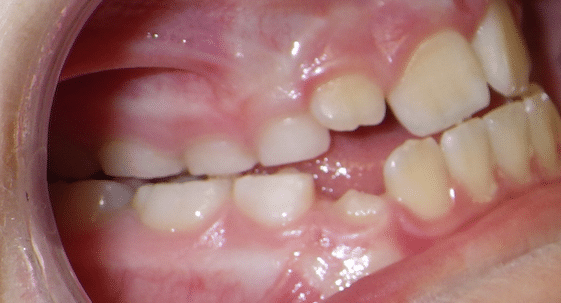

Our patient, Luke, presented with an underbite. We began Phase I with him in October 2018 and were able to achieve major changes in Luke’s profile and bite. Also note how his upper lip changed as well. Luke’s photos show how well growth modification can work in an adolescent patient, even preventing the need for jaw surgery as an adult.